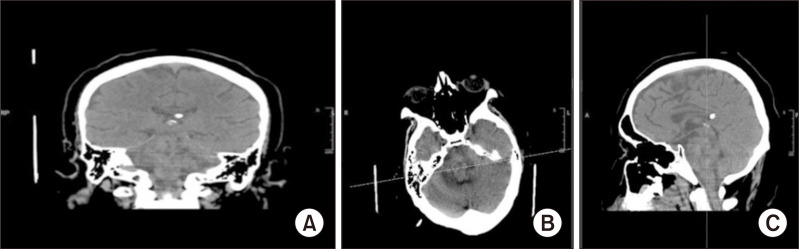

Nystagmus, characterized by involuntary eye movements, can arise from several causes, with benign paroxysmal positional vertigo being the most prevalent. Additionally, central lesions such as tumors may also induce nystagmus. This case report describes the amelioration of vertical nystagmus in a patient with advanced glioma after treatment with the GABAergic drug baclofen.